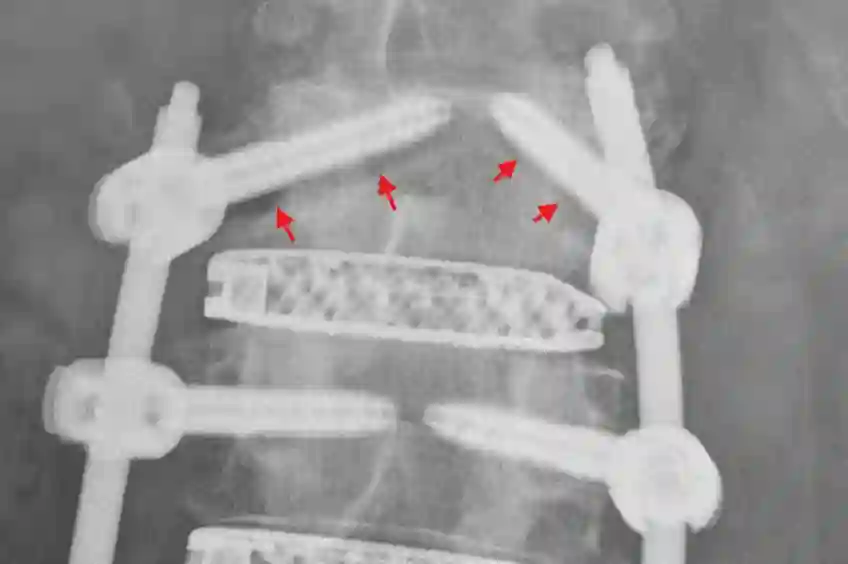

Pedikelschraubenfehllage

Pedikelschraubenmigration

Als Pedikelschraubenmigration bezeichnet man das "wandern" der Pedikelschraube von der ursprünglichen Position.